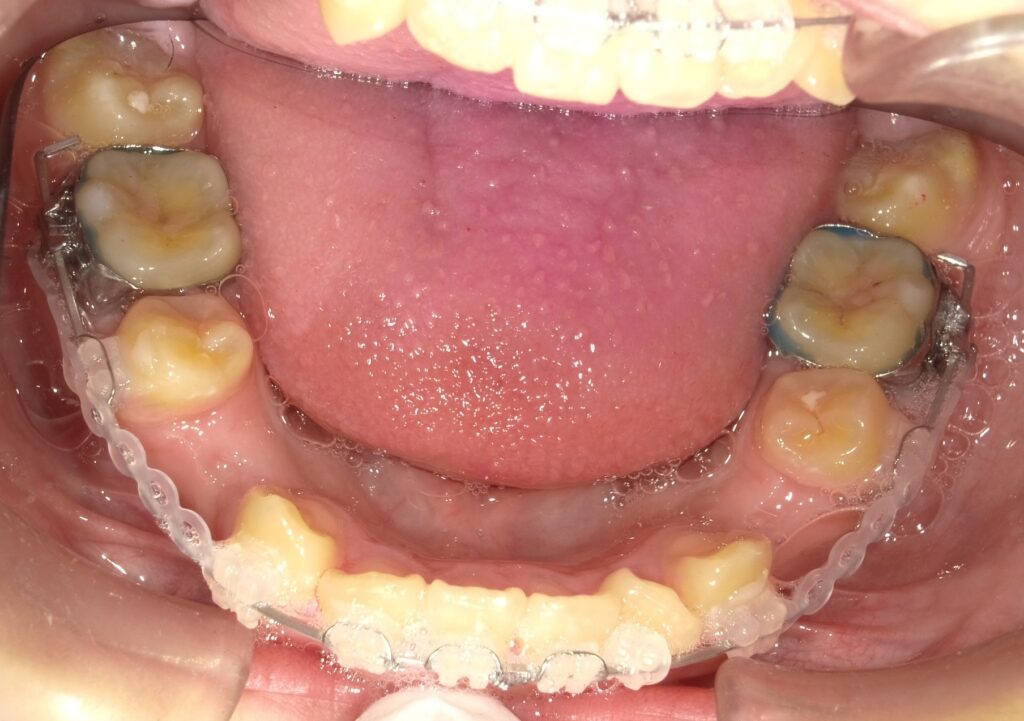

画像のようにリング状のゴミで前歯を後ろに交代させます。